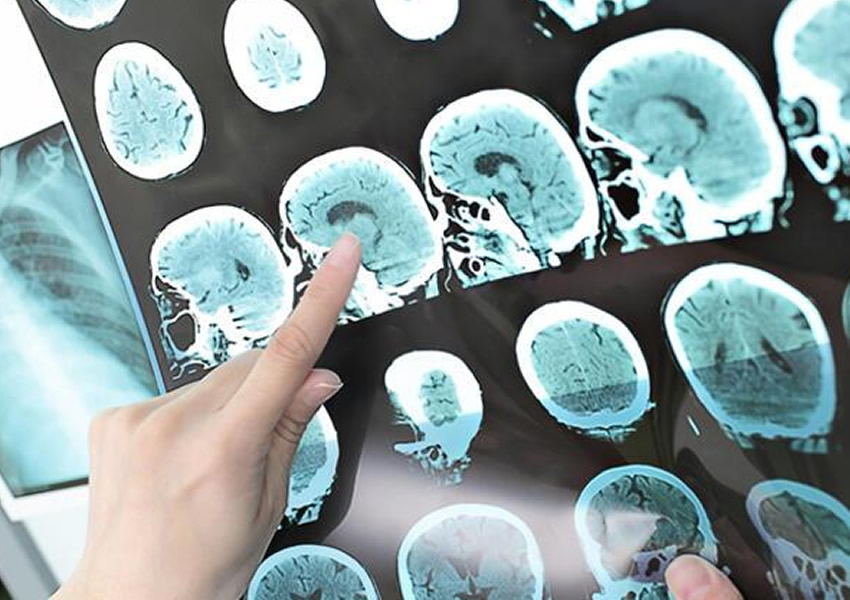

- Hazırlık: Ameliyat öncesinde hasta detaylı şekilde incelenir. MR ve fonksiyonel görüntüleme yöntemleriyle tümörün konumu belirlenir.